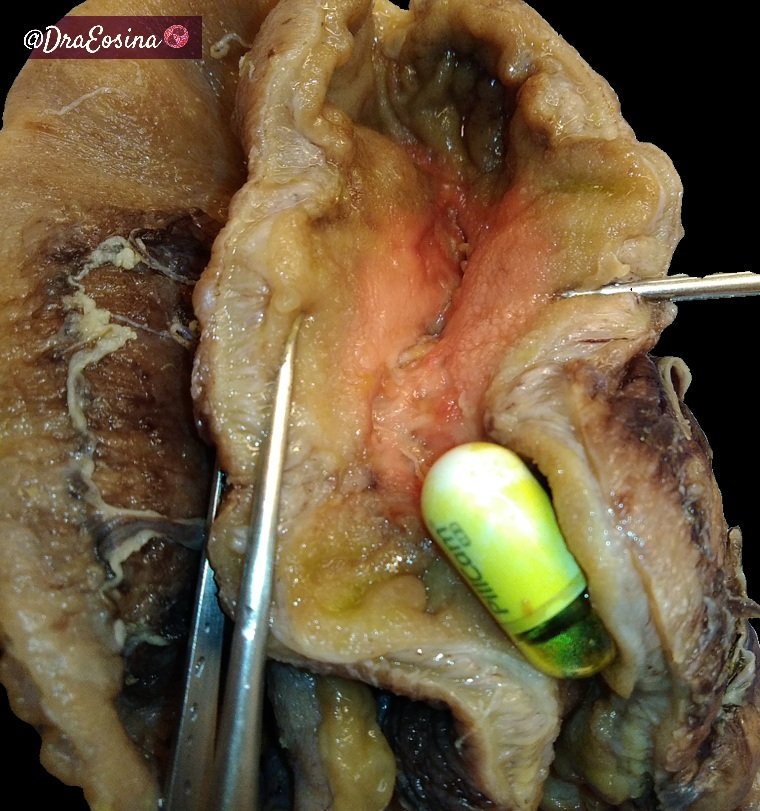

#neuropathology conference with the #LivingLegend Dr. J.L Perez-Berenguer Today's topic: Astrocytic lesions/tumors #pathology #neuropath #neuro #residentlife #PerezBerenguer Karra Jones, MD, PhD Fausto Rodriguez AANP Hopkins Neuropath